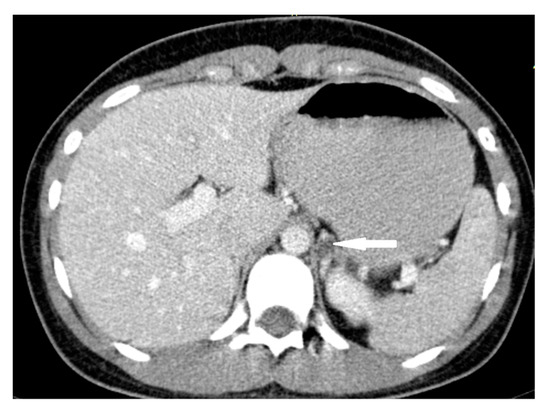

2.1. Case 1

2.2. Case 2

2.3. Case 3

2.4. Case 4

2.5. Case 5

2.6. Case 6

2.7. Case 7